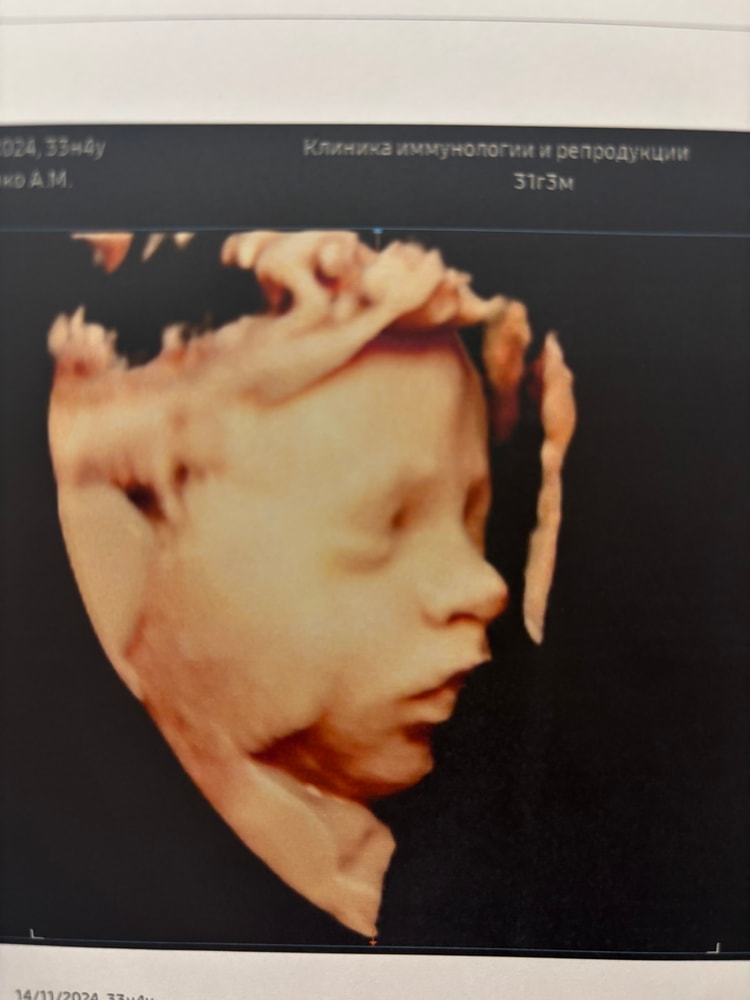

3D УЗИ в 33-34 недели.

Анна, моя двойня на 33 неделе. Все видно 👍🏻